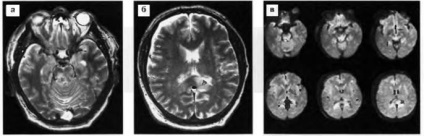

Ábra. 22. Egy kis intracerebralis hematóma a bal frontális régióban. MRI dinamika: a, b - az első nappal a sérülés után: T2 mód haematoma van egy alacsony jel T1 üzemmód - jelet haematoma izointensivny, perifocal ödéma T2 - giperintensiven MRI 7 nappal a trauma után (c, d) - haematoma ez hyperintensive jel mindkét üzemmódban miatt methemoglobinná.

Ábra. 23. Diffusion axonok sérülés a corpus callosum. T2-súlyozott MRI: növekvő jel rész a corpus callosum görgő, szubdurális vérömleny a frontális.

Ábra. 24. Diffúziós axonális agysérülés. T2-súlyozott MRI (a, b) - részletekben enyhén csökkent perifocal jel hiperintenzív jel a jobb lábbal, és a bal agy fele görgő callosum, szubdurális vérömleny a jobb Front-temporális terület; a - MRT (sorozat szeletek) módban DBU: megnövekedett jelet részletekben alacsony jel punctata gócok az agyban lábak (d> s) és a görgő callosum.